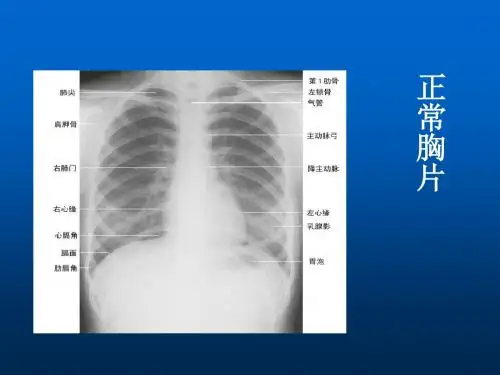

医学影像学包括: X线诊断 超声诊断 X线计算机体层摄影(CT) 核磁共振(MRI) 介入放射学 核医学